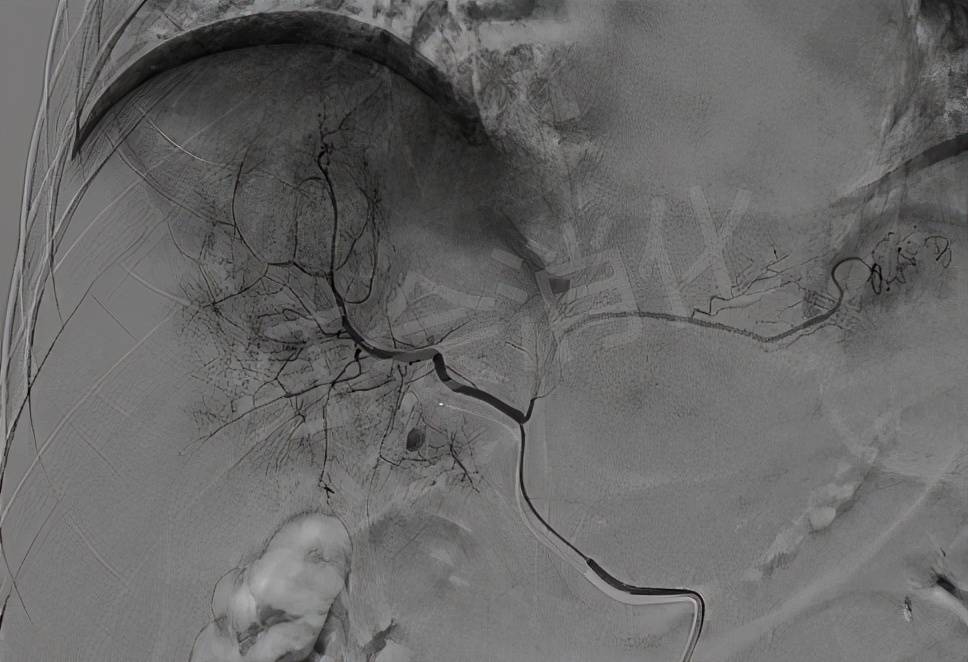

超选肿瘤供血动脉造影 , 可见肿瘤染色明显 , 予以灌注化疗栓塞治疗

文章图片

栓塞后肝动脉造影 , 肿瘤周围的动脉丛消失 , 动脉化疗栓塞成功